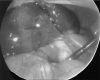

Torsion of the gallbladder is a rare entity that is difficult to diagnose preoperatively. The condition occurs most often in the elderly. Although its etiology is unknown, a constant finding is the presence of the gallbladder on a mobile mesentery (floating gallbladder). Torsion, or volvulus, of the gallbladder occurs when it twists axially, with the subsequent occlusion of bile and/or blood flow. Herein, a case of torsion of the gallbladder is presented where preoperative computed tomographic scan and laparoscopy were successfully used to diagnose and treat this condition without the usual requirement of open exploration. Given the possibility of laparoscopic cholecystectomy and the increasing incidence with which torsion of the gallbladder is being witnessed today, the importance of a preoperative computed tomographic scan is emphasized when there is a high index of clinical suspicion.